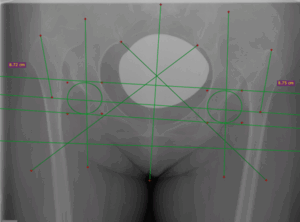

Для хирургического лечения диспластического коксартроза IV типа по Crowe разработан усовершенствованный деротационный имплантат, предназначенный для фиксации зоны подвертельной остеотомии. Биомеханические расчёты подтвердили прочностную надёжность конструкции, а первые операции продемонстрировали её высокую эффективность в стабилизации костных фрагментов при сложной анатомии. На данный момент ведётся клиническая апробация.

Строение стабилизирующей пластины для остеосинтеза зоны остеотомии при диспластических коксартрозах IV типа по Crowe